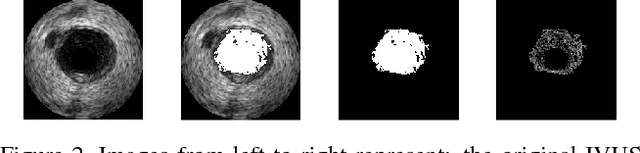

Abstract:Intravascular Ultrasound (IVUS) is an intra-operative imaging modality that facilitates observing and appraising the vessel wall structure of the human coronary arteries. Segmentation of arterial wall boundaries from the IVUS images is not only crucial for quantitative analysis of the vessel walls and plaque characteristics, but is also necessary for generating 3D reconstructed models of the artery. The aim of this study is twofold. Firstly, we investigate the feasibility of using a recently proposed region detector, namely Extremal Region of Extremum Level (EREL) to delineate the luminal and media-adventitia borders in IVUS frames acquired by 20 MHz probes. Secondly, we propose a region selection strategy to label two ERELs as lumen and media based on the stability of their textural information. We extensively evaluated our selection strategy on the test set of a standard publicly available dataset containing 326 IVUS B-mode images. We showed that in the best case, the average Hausdorff Distances (HD) between the extracted ERELs and the actual lumen and media were $0.22$ mm and $0.45$ mm, respectively. The results of our experiments revealed that our selection strategy was able to segment the lumen with $\le 0.3$ mm HD to the gold standard even though the images contained major artifacts such as bifurcations, shadows, and side branches. Moreover, when there was no artifact, our proposed method was able to delineate media-adventitia boundaries with $0.31$ mm HD to the gold standard. Furthermore, our proposed segmentation method runs in time that is linear in the number of pixels in each frame. Based on the results of this work, by using a 20 MHz IVUS probe with controlled pullback, not only can we now analyze the internal structure of human arteries more accurately, but also segment each frame during the pullback procedure because of the low run time of our proposed segmentation method.

Abstract:This work concentrates on Extremal Regions of Extremum Level (EREL) selection. EREL is a recently proposed feature detector aiming at detecting regions from a set of extremal regions. This is a branching problem derived from segmentation of arterial wall boundaries from Intravascular Ultrasound (IVUS) images. For each IVUS frame, a set of EREL regions is generated to describe the luminal area of human coronary. Each EREL is then fitted by an ellipse to represent the luminal border. The goal is to assign the most appropriate EREL as the lumen. In this work, EREL selection carries out in two rounds. In the first round, the pattern in a set of EREL regions is analyzed and used to generate an approximate luminal region. Then, the two-dimensional (2D) correlation coefficients are computed between this approximate region and each EREL to keep the ones with tightest relevance. In the second round, a compactness measure is calculated for each EREL and its fitted ellipse to guarantee that the resulting EREL has not affected by the common artifacts such as bifurcations, shadows, and side branches. We evaluated the selected ERELs in terms of Hausdorff Distance (HD) and Jaccard Measure (JM) on the train and test set of a publicly available dataset. The results show that our selection strategy outperforms the current state-of-the-art.